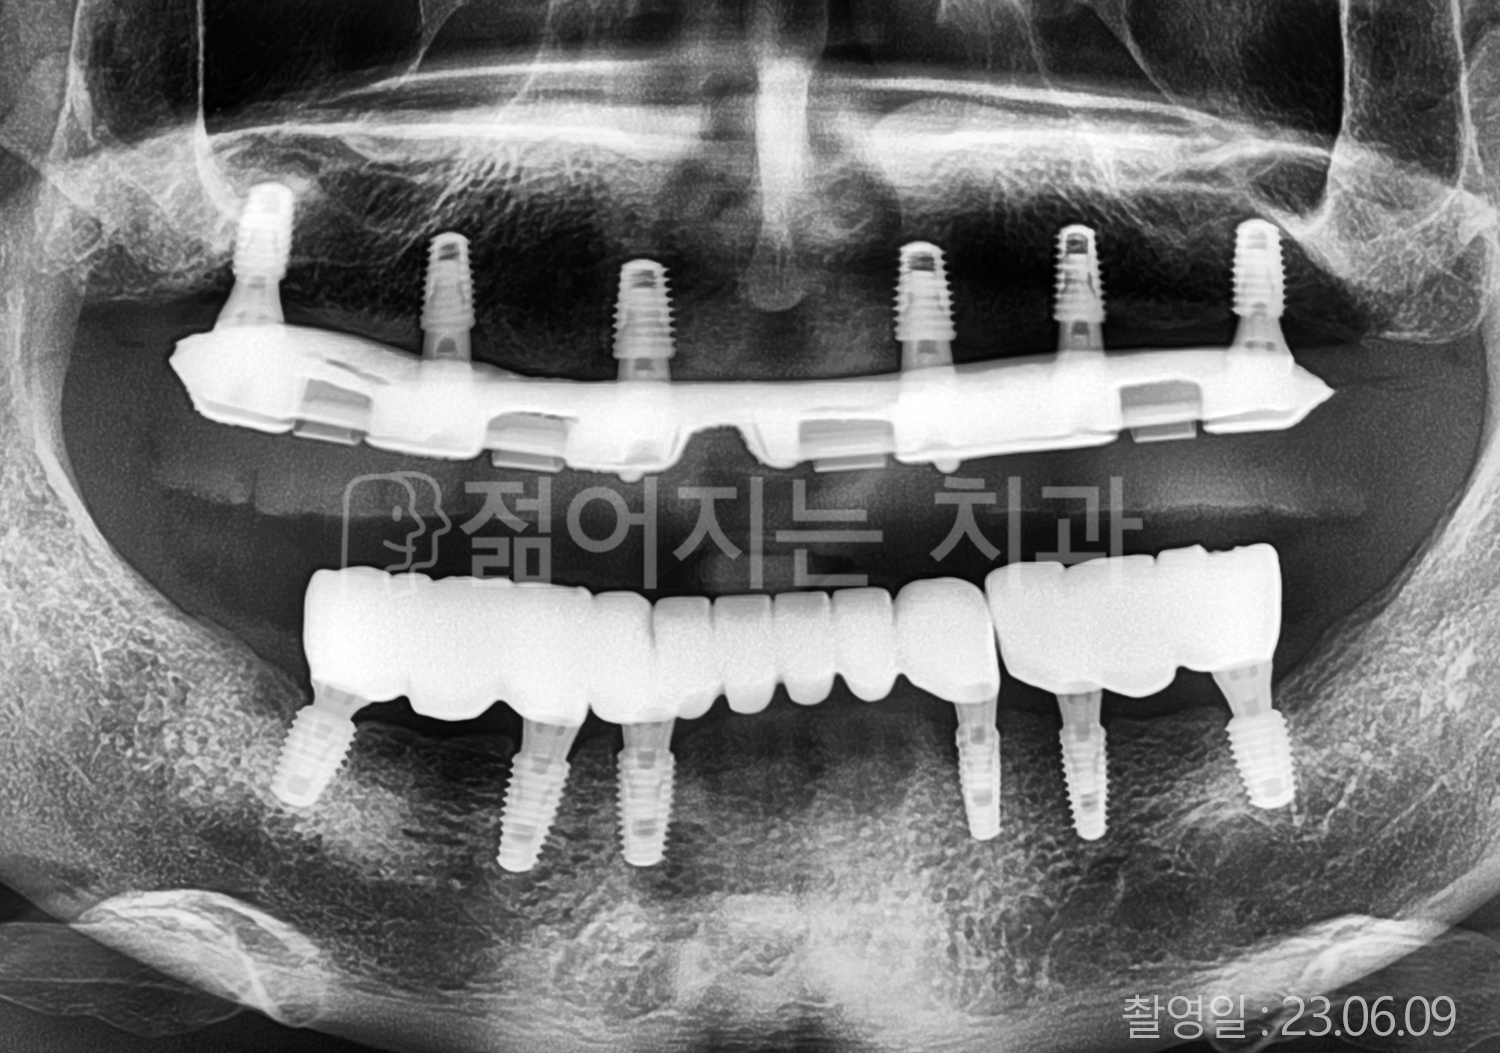

• 60대 고혈압, 고지혈증 전체치아 10개 이상 임플란트

• 70대 전체치아 10개 이상 임플란트

• 60대 전체치아 10개 이상 임플란트

• 50대 전체치아 10개 이상 임플란트

• 50대 고혈압, 고지혈증 전체치아 10개 이상 임플란트

• 60대 고혈압, 당뇨, 고지혈증 전체치아 10개 이상 임플란트

• 80대 고혈압, 당뇨, 골다공증 전체치아 10개 이상 임플란트

• 60대 고혈압 전체치아 10개 이상 임플란트

• 60대 고지혈증 전체치아 10개 이상 임플란트

• 60대 당뇨 전체치아 10개 이상 임플란트